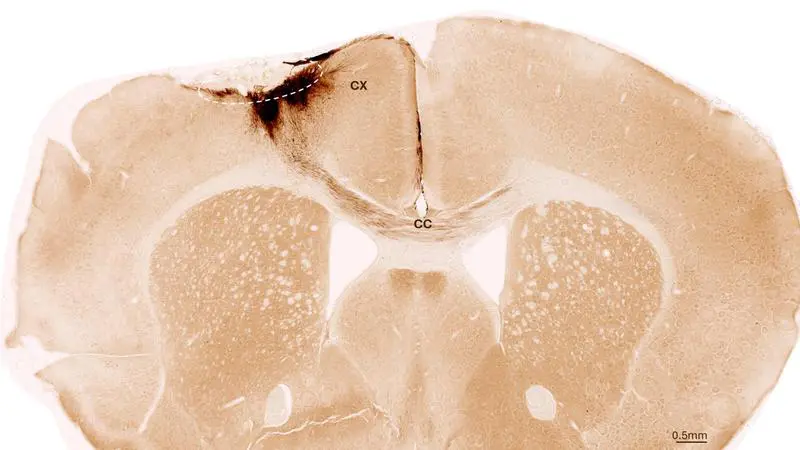

World’s first shunt operation with microsurgical robotic system at the UKSH

At the University Medical Center Schleswig-Holstein (UKSH), Kiel Campus, a shunt operation was performed for the first time in the world with the microsurgical "Symani Surgical System". Two patients had a dialysis shunt, a connection between the artery and the vein...